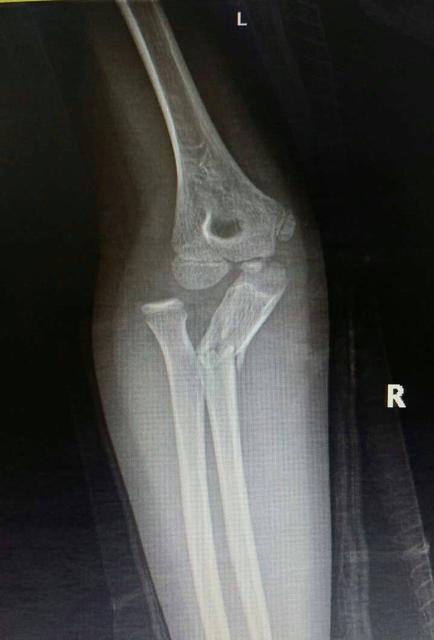

但如果孩子的骨折合并有血管损伤的开放性骨折(皮肤破了,骨头与外界有接触),或是伤后出现骨筋膜室综合征早期征象的患儿,急诊手术是必须的。家长也不应惧怕创伤性的手术,耽误治疗的最佳时机。

2、开放性骨折要先将患处包扎好(可用清洁、干净的布片),再以夹板固定。无夹板可用木棍、树枝、竹竿等代替。包扎时,要在夹板上垫以衣服等软物,防止皮肤受损。同时要注意把伤肢的上下两关节固定起来(先绑骨折上端,后绑下端)。如遇骨折端外露,注意不要将骨折端放回伤口内,以免将细菌带入伤口深部引起深部感染,应继续保持外露。